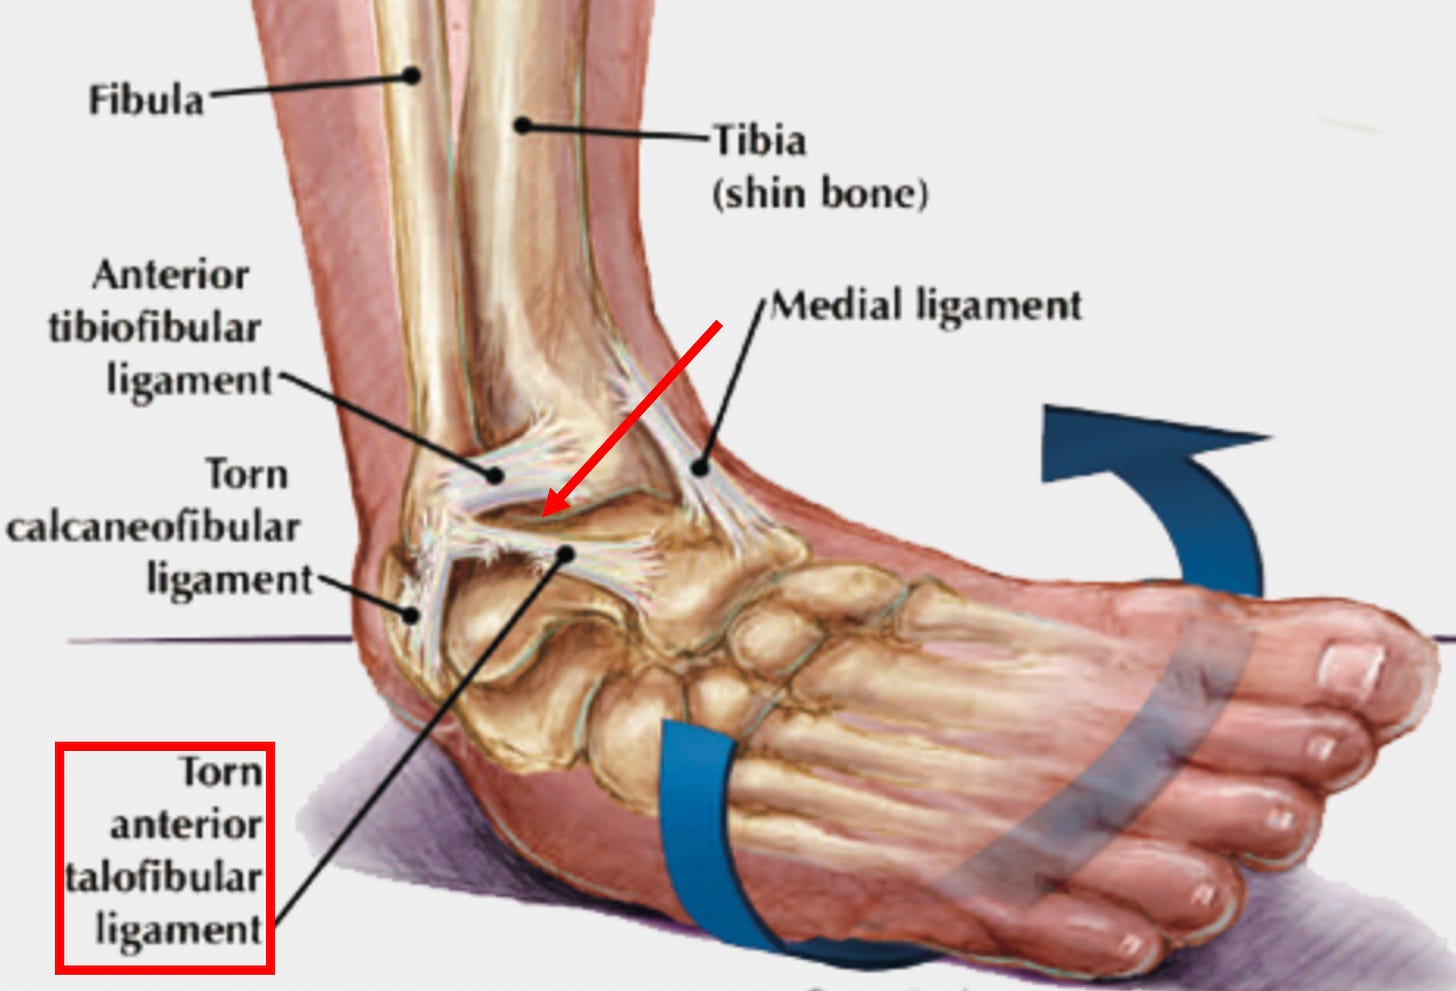

Ligamentous weakness is frequently caused by a chronic injury to a ligament (or an injury which did not properly heal). For example, when the ankle is injured from a sprain, the ligament that keeps the ankle from turning inwards gets damaged, predisposing us to an unstable ankle and future ankle injuries until the ligament is repaired and strengthened with an appropriate regenerative therapy.

This results in sprains that are treated with NSAIDs often being predisposed to future injuries (since the stability given to the joint by those ligaments is partially lost until something like a regenerative therapy is given to repair that ligament)—which in the case of ankle sprains is something I and colleagues frequently see in our patients.